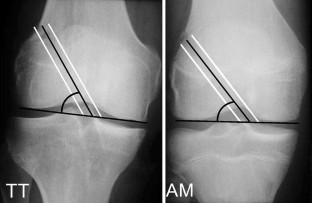

Correct placement of the tibial and femoral bone tunnel is prerequisite to a successful anterior cruciate ligament (ACL) reconstruction. This study compares the resulting radiographic femoral bone tunnel position of two commonly used techniques for arthroscopically assisted drilling of the femoral bone tunnel: the transtibial approach or drilling through the anteromedial arthroscopy portal. The resulting bone tunnel position was assessed in postoperative knee radiographs of 70 patients after ACL reconstruction. Three independent observers identified the femoral bone tunnel and determined its position in the lateral and A–P view. Differences in femoral tunnel position between transtibial and anteromedial drilling were evaluated. In the sagittal plane, significantly more femoral bone tunnels were positioned close to the reference value using an anteromedial drilling technique (86%) when compared to transtibial drilling (57%). Drilling through the transtibial tunnel resulted in a significantly more anterior position of the femoral tunnel. In the frontal plane, femoral bone tunnels which were placed through the anteromedial arthroscopy portal displayed a significantly greater angulation towards the lateral condylar cortex (50.92°) when compared to transtibial drilling (58.82°). In conclusion, drilling the femoral tunnel through the anteromedial arthroscopy portal results in a radiographic femoral bone tunnel position which is suggested to allow stabilization of both anterior tibial translation and rotational instability when using a single bundle reconstruction technique. Further studies may evaluate if there are any clinical advantages using the anteromedial portal technique.

Fig. 4